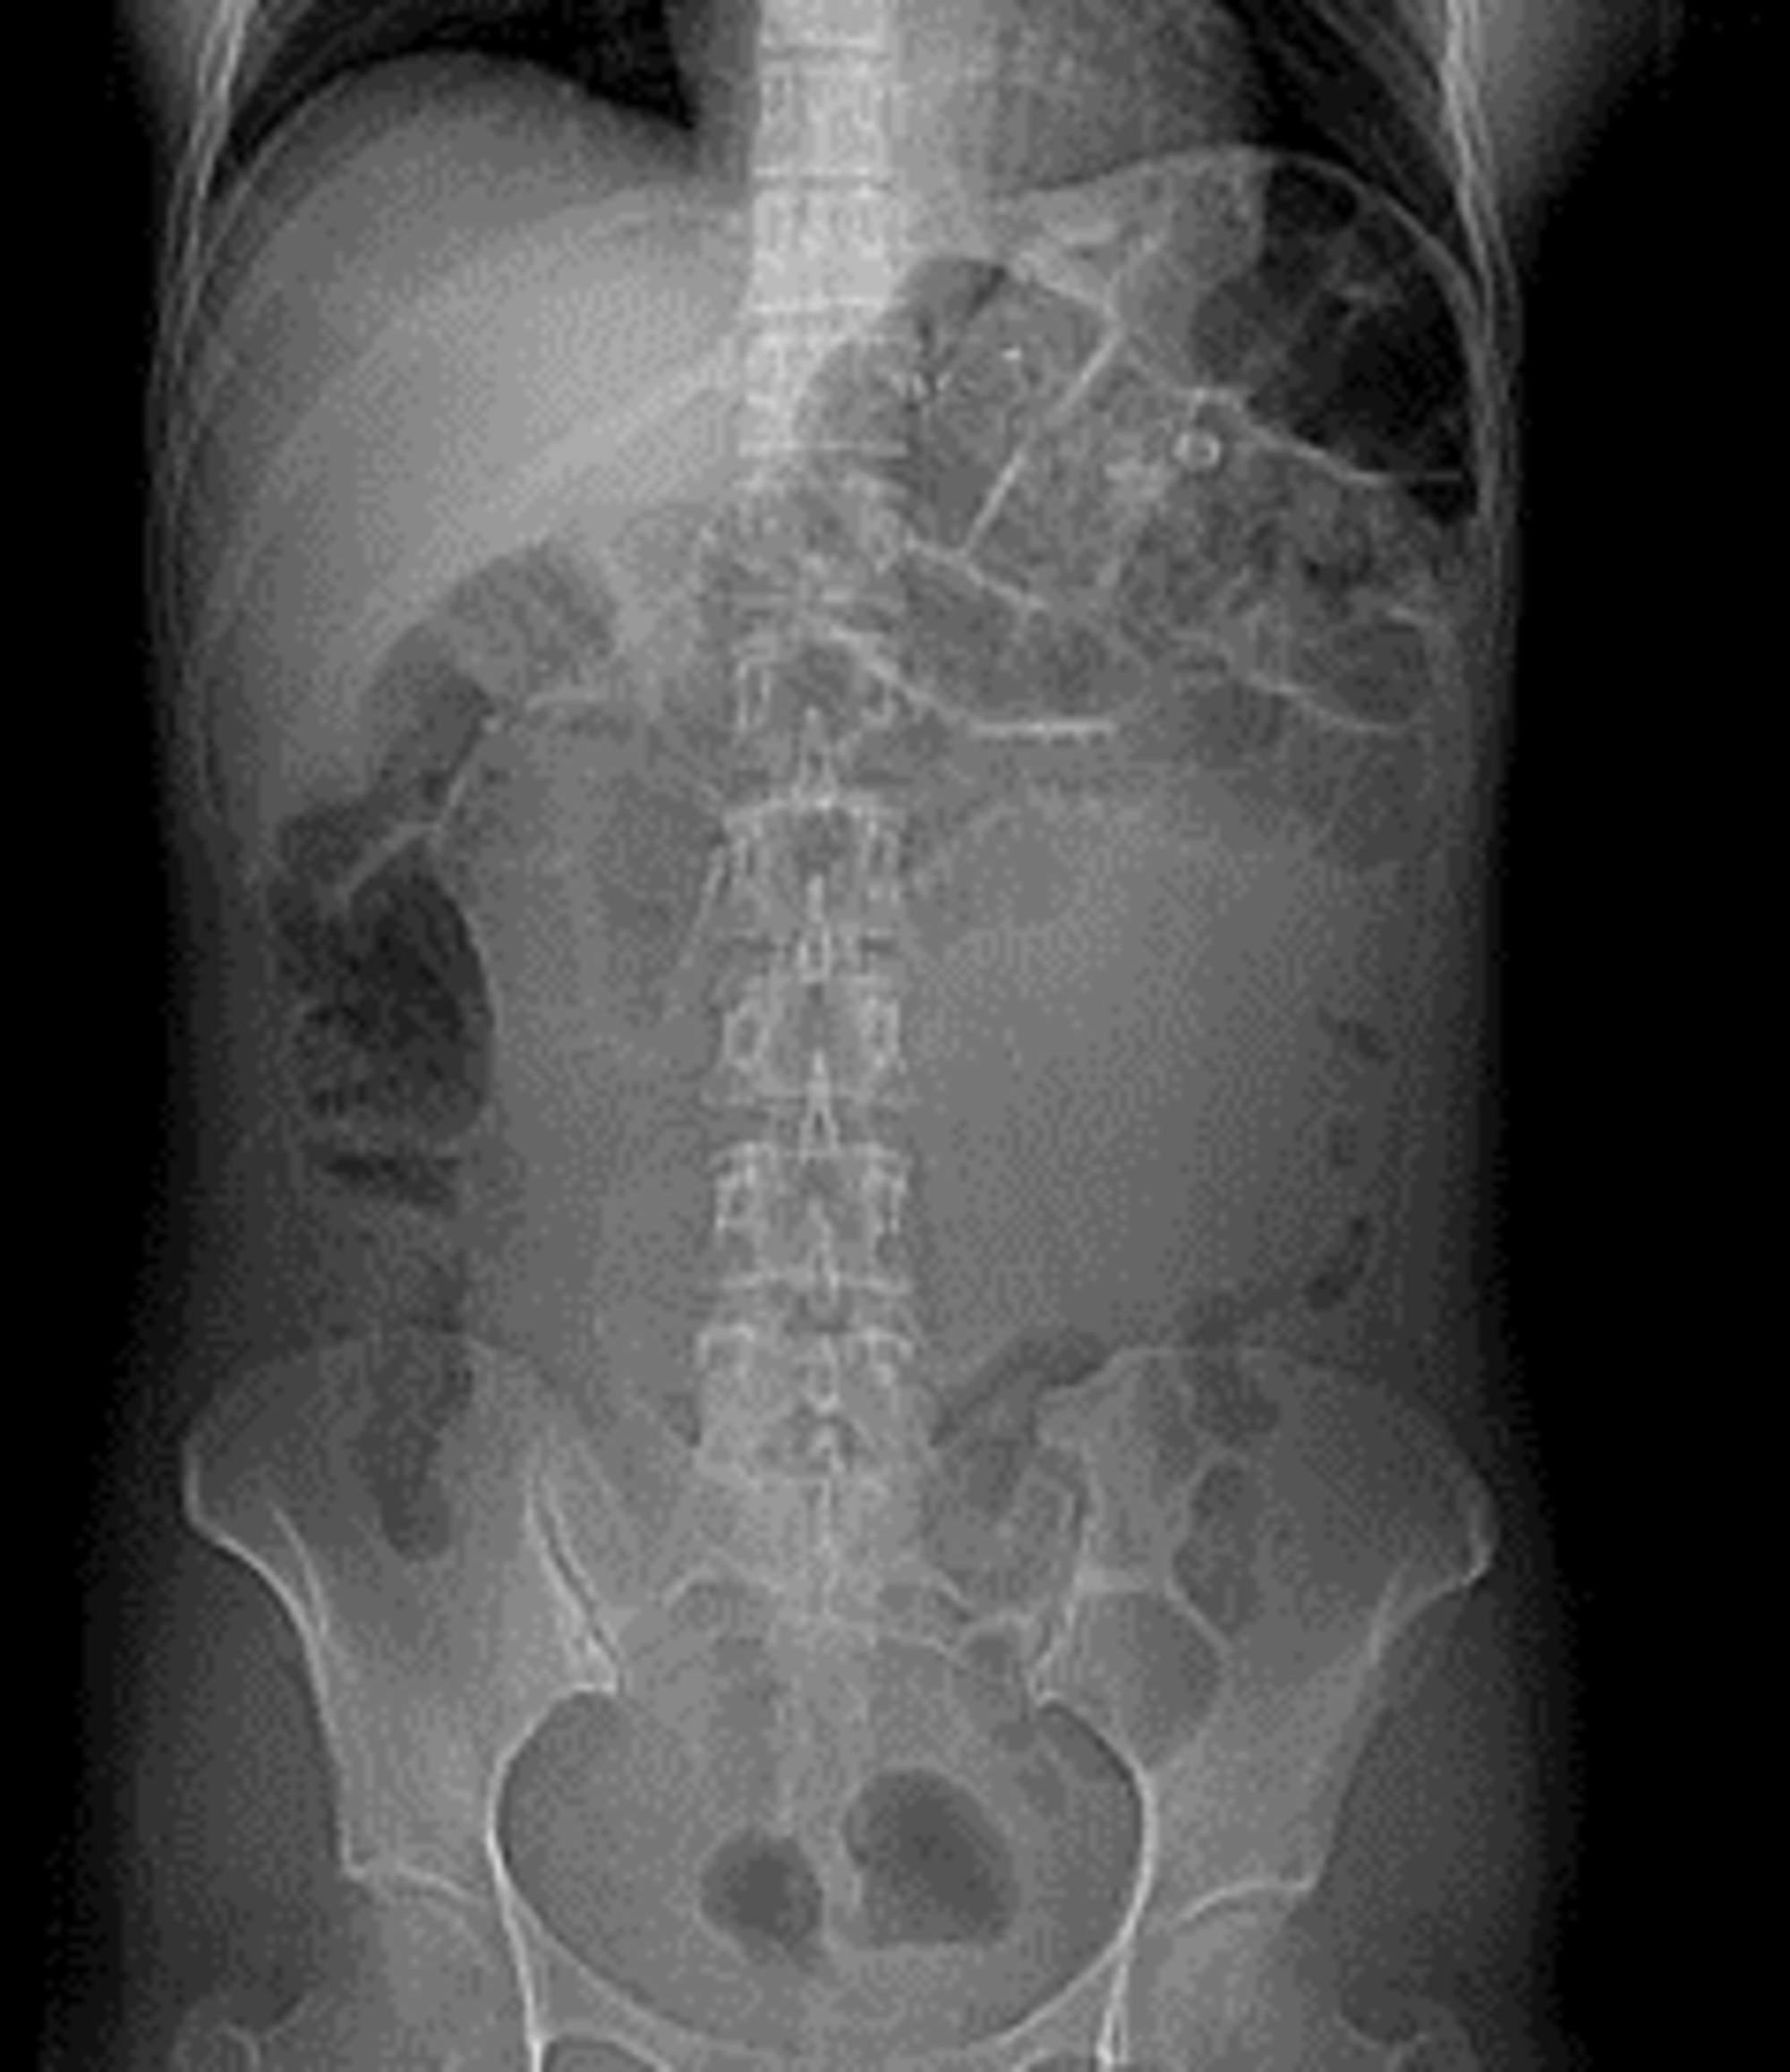

Gastric Bypass Surgery, Xray Photograph by Zephyr Fine Art America X Ray After Gastric Sleeve Laparoscopic sleeve gastrectomy is one of the most common bariatric procedures worldwide. This paper seeks to describe the radiological evaluation of the main bariatric surgeries, primarily done using fluoroscopic upper. Another option is built upon the similarity of the gastric sleeve to a cylinder and uses the following formula: This topic review will present the normal and abnormal findings seen. X Ray After Gastric Sleeve.

Gastric bypass surgery, Xray Stock Image C010/4920 Science Photo X Ray After Gastric Sleeve This paper seeks to describe the radiological evaluation of the main bariatric surgeries, primarily done using fluoroscopic upper. Laparoscopic sleeve gastrectomy is one of the most common bariatric procedures worldwide. Another option is built upon the similarity of the gastric sleeve to a cylinder and uses the following formula: It has recently gained in popularity. In addition, we describe the. X Ray After Gastric Sleeve.

Gastric bypass surgery, Xray Stock Image C010/4919 Science Photo X Ray After Gastric Sleeve This paper seeks to describe the radiological evaluation of the main bariatric surgeries, primarily done using fluoroscopic upper. V = π × r 2 × h, where v = gastric. Laparoscopic sleeve gastrectomy is one of the most common bariatric procedures worldwide. In addition, we describe the imaging features of the most common early and late postoperative complications, including anastomotic. X Ray After Gastric Sleeve.

Radiology of the Laparoscopic RouxenY Gastric Bypass Procedure X Ray After Gastric Sleeve It has recently gained in popularity. Laparoscopic sleeve gastrectomy is one of the most common bariatric procedures worldwide. V = π × r 2 × h, where v = gastric. This topic review will present the normal and abnormal findings seen on radiologic evaluation after gastric banding, gastric bypass,. In addition, we describe the imaging features of the most common. X Ray After Gastric Sleeve.